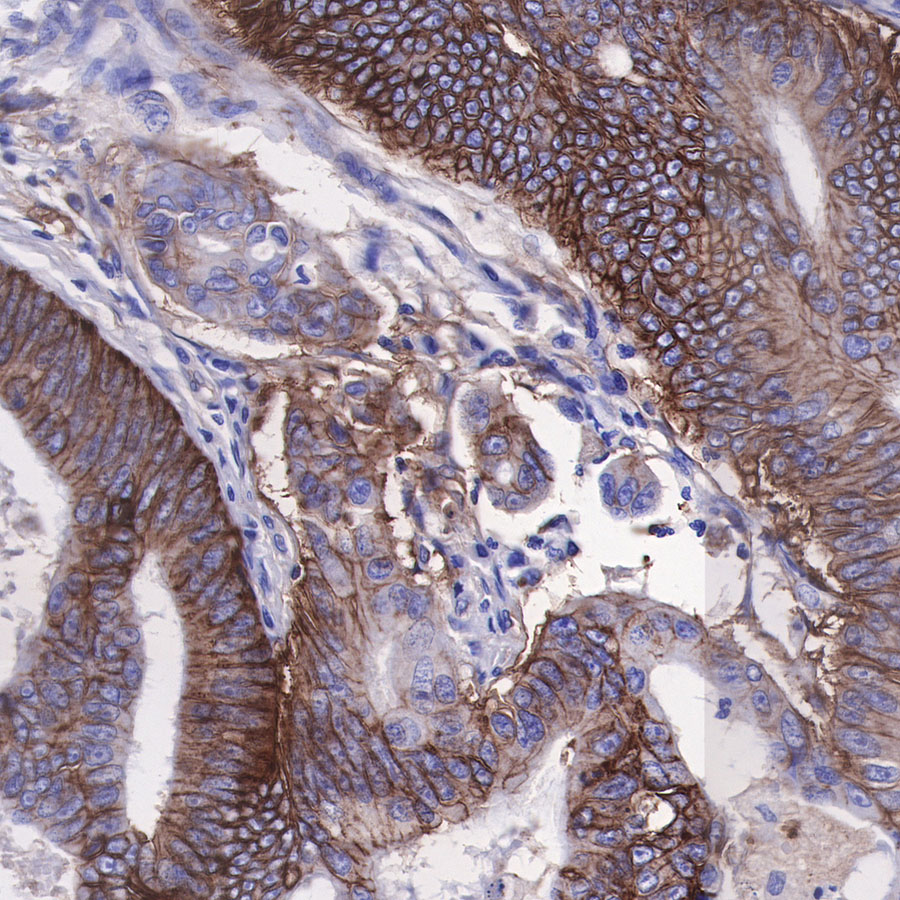

| IHC-P |

1:500 |

|